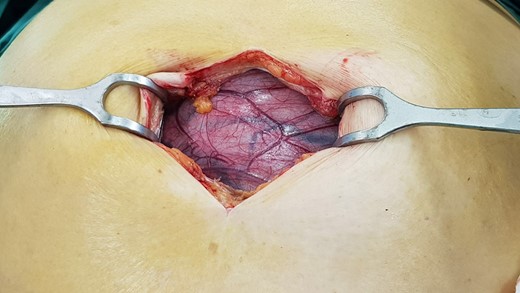

A laparotomy was performed to resect the cyst for diagnostic and therapeutic purposes (Figs 2 and 3). The cyst was noted to originate from the sigmoid mesocolon. No other viscera required resection. The patient made an uneventful recovery.

Macroscopically, there was an intact cystic structure containing clear yellowish serous fluid. The internal surface was smooth with wall thickness of up to 10 mm. On microscopy, the cyst was lined by a single layer of columnar cells with apical mucin and had surrounding ovarian stroma. There was no evidence of malignancy. The cystic tumour was confirmed to be a benign mucinous cystadenoma of the ovary arising from the sigmoid mesocolon.